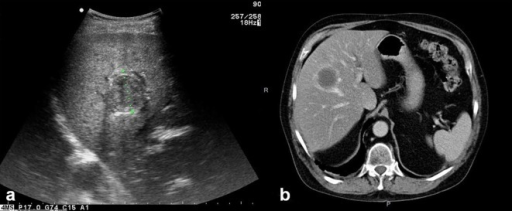

Puzzle 37

What's the Diagnosis?